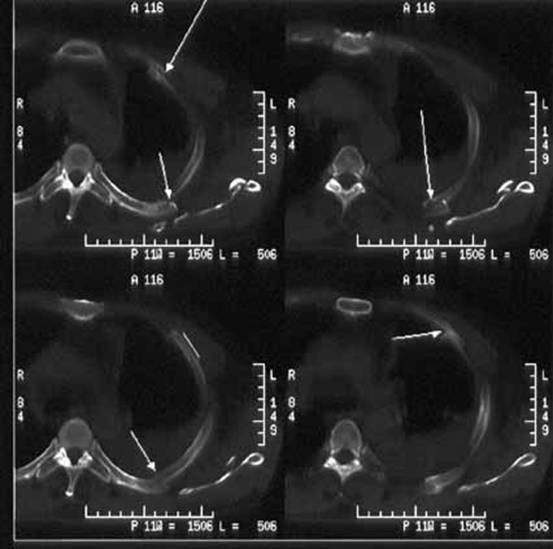

Msct对疑似肋骨骨折伪影的分析

多层螺旋ct后处理技术在肋软骨骨折伤情鉴定中的应用

Span Class Emphasis Bold 肋骨骨折 Span Dr Span Class Emphasis Bold 与 Span Ct Span Class Emphasis Bold 影像的对比效果研究 Span

多层螺旋ct三维重建技术诊断创伤性肋骨骨折的临床价值分析 参考网

多层螺旋ct三维重建技术在胸部外伤的诊断价值